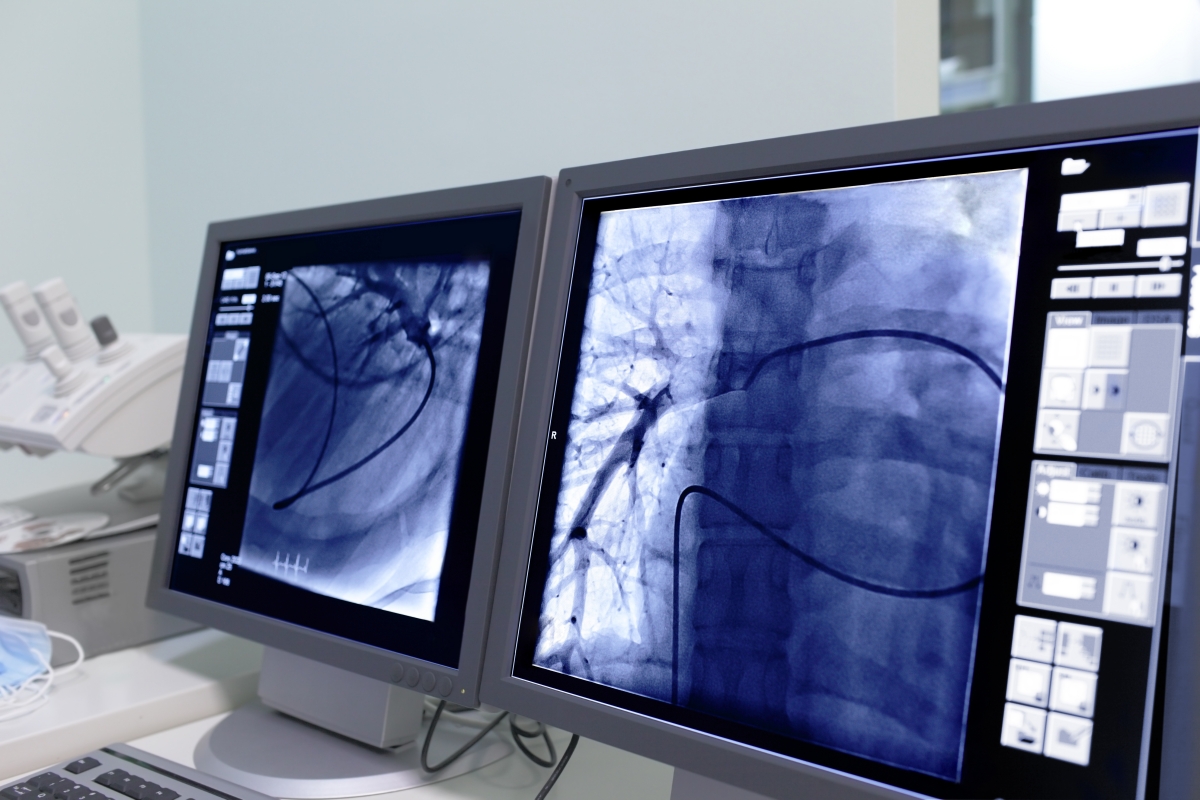

Рентгенэндоваскулярная хирургия (РЭХ) – это метод выполнения оперативного лечения через сосуды.

Этот способ лечения позволяет проводить хирургические манипуляции через прокол на руке или на бедре, размер которого составляет всего 3 мм. Для контроля над оперативным вмешательством используется высокотехнологичное рентгеноборудование.

В настояший момент, такие хирургические манипуляции как коронарография и стентирование коронарных (сердечных) артерий являются "золотым стандартом" в лечении пациентов с ишемической болезнью сердца и инфарктом миокарда.